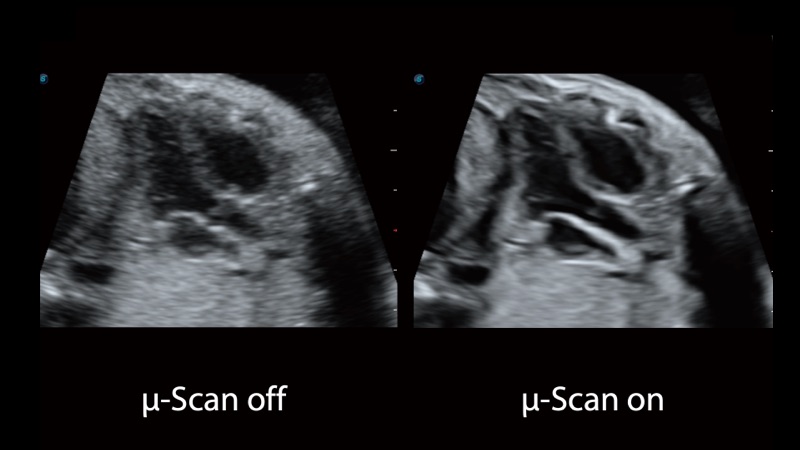

单晶体凸阵探头

凭借开立医疗先进的成像技术和优异的探头技术提供的清晰的图像表现,您可以更自信地做出临床决策。